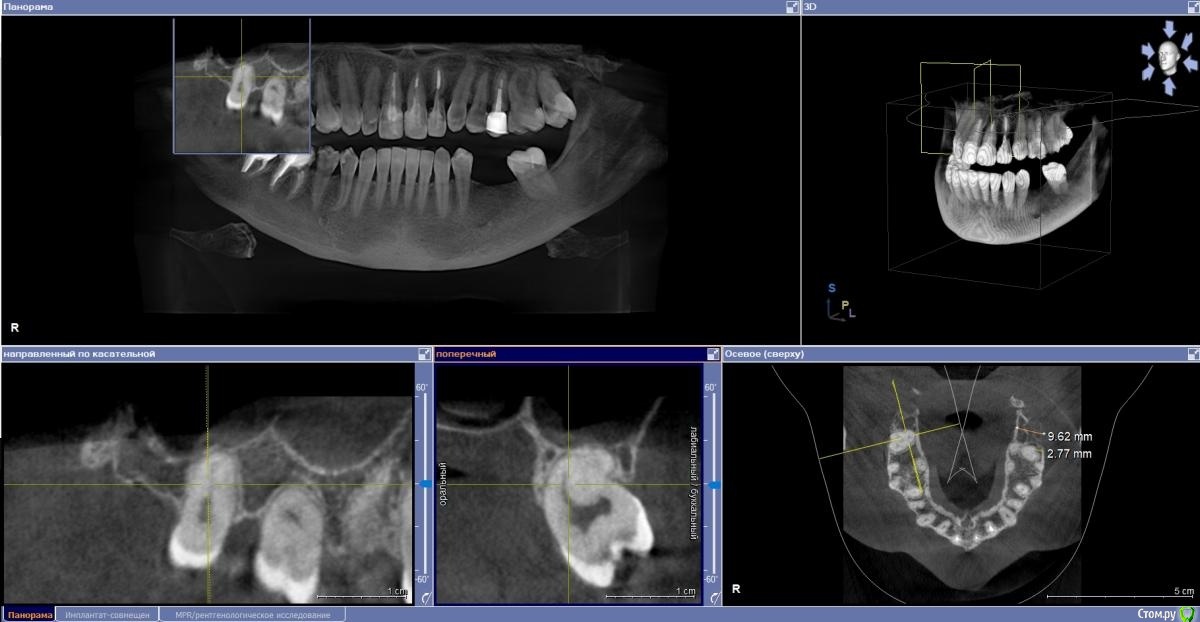

Fin Опубликовано 4 ноября, 2020 Поделиться Опубликовано 4 ноября, 2020 (изменено) Здравствуйте коллеги. В клинику обратилась пациентка с жалобой на эстетику передних зубов. В ходе осмотра и составления плана на КТ обнаружилась резка корня 22. Перфорация вестибулярной стенки на КТ не наблюдается. Думаю что при полном удалении корня вестибулярная стенка тоже уйдет. Техника IDR и B2S невозможна т.к. присутствуют восьмые зубы.Как вы считаете, стоит ли попытка сделать одномоментную имплантацию с техникой вариантов корневого щита или все таки идти на полное удаление? Изменено 4 ноября, 2020 пользователем Fin Ссылка на комментарий

Fin Опубликовано 5 ноября, 2020 Автор Поделиться Опубликовано 5 ноября, 2020 зависит от ваших мануальных навыковкроме техник IDR и щита есть и классические вполне рабочие методикизапланируйте щит, если не получится будьте готовы сделать имплантацию + алло или ксено графт сст даже при наличии 8 можно забрать Есть восьмёрки - разве это противопоказание к idr? Это показание к удалению 8х)Почему то не получилось приложить скрины в первом сообщении. Мне кажется в области 8го зуба забирать нечего за ним уже как то далековато. Как Вы считаете? Ссылка на комментарий

Fin Опубликовано 10 ноября, 2020 Автор Поделиться Опубликовано 10 ноября, 2020 (изменено) Нет тут места и на щит, и на имплантатНе понял Вас. Между корнями около 8 мм , 3.5 должен пройти. Больше беспокоит что после полного удаления корня образуется перфорация кортикальной стенки. Изменено 10 ноября, 2020 пользователем Fin Ссылка на комментарий